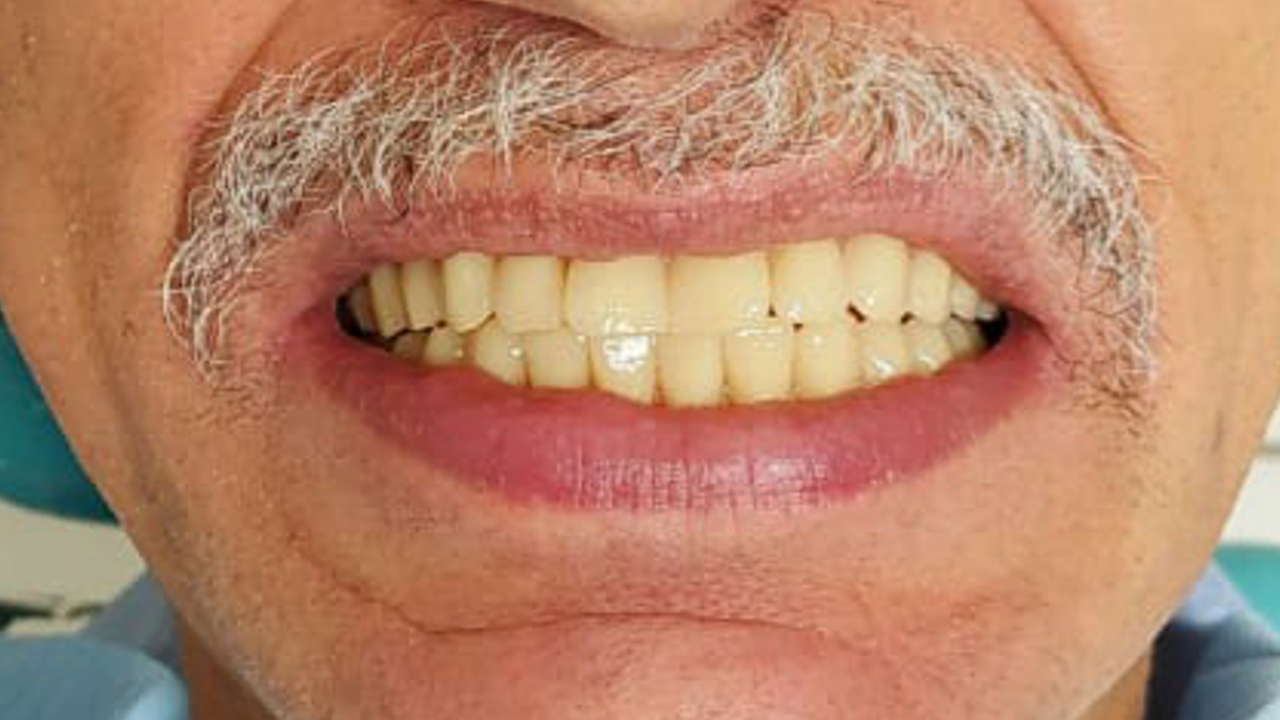

PROTOCOLO é um tipo de prótese que fica presa por implantes, substituindo a dentadura móvel. Ou seja, DISPENSA o uso de pastas ou adesivos fixadores. Só o dentista consegue por e tirar a prótese da sua boca!😷 Além disso, o PROTOCOLO, melhora a mastigação e a fala,

melhorando a qualidade de VIDA dos pacientes.